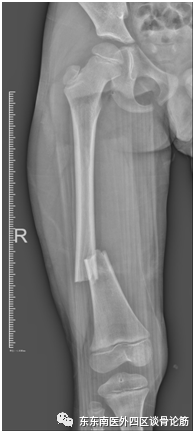

近日,我科收治了一名因房屋倒塌不慎造成右股骨干骨折的6岁男童,涛涛。

(受伤的X线片)